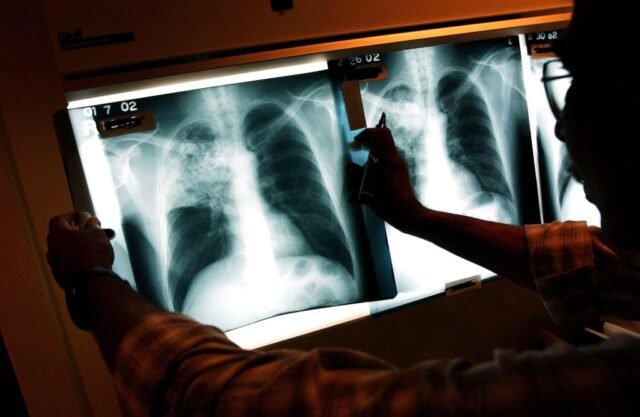

La primera es la capacidad de buscar atención oportuna cuando algo anda gravemente mal. Los estudios muestran que las personas sin cobertura a menudo retrasan o evitan ir al hospital cuando tienen síntomas graves como dolor en el pecho o dificultad para respirar, debido al costo. Estos retrasos pueden ser mortales: el tratamiento oportuno de ataques cardíacos, accidentes cerebrovasculares y otras emergencias es una de las formas más efectivas en que los seguros reducen la mortalidad.

Los seguros también desempeñan un papel crucial en la detección de enfermedades graves mientras aún son tratables. Es mucho más probable que las personas busquen atención preventiva cuando el seguro la hace asequible (o, como ha demostrado nuestra propia investigación, cuando el seguro la hace gratuita). Un estudio de JAMA Oncology de 177.075 mujeres encontró que aquellas sin seguro privado tenían muchas más probabilidades de ser diagnosticadas con cáncer avanzado, lo que resultaba en tasas de supervivencia mucho más bajas que las mujeres con cobertura integral.